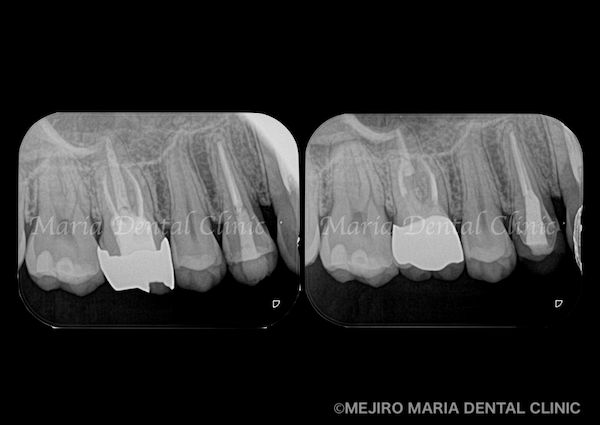

【症例】セラミック治療後に発症した根尖性歯周炎に対する歯根端切除術